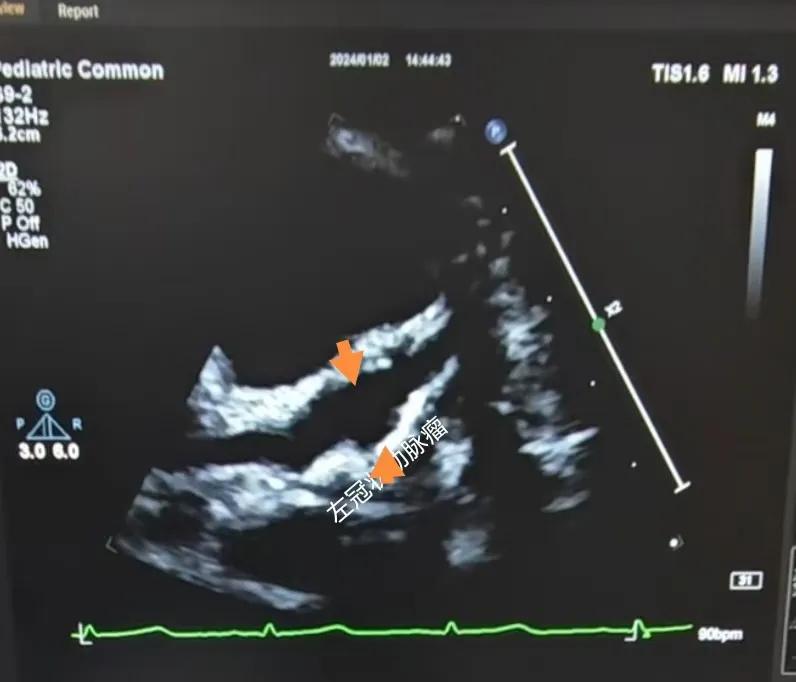

(川崎病患兒:左冠狀動脈瘤)